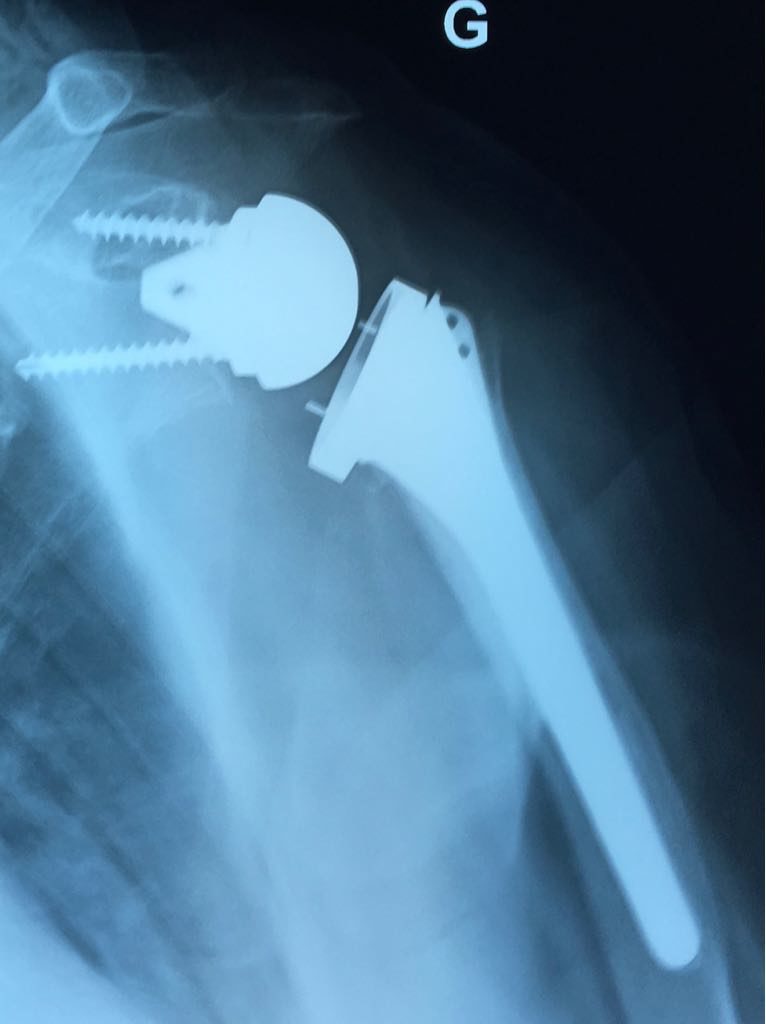

Cliquer sur une photo pour défiler la collectionOmarthrose excentree sur rupture massive de coiffe des rotateurs, femme âgée de 78 ans

Prothèse totale épaule inversée non cimentée